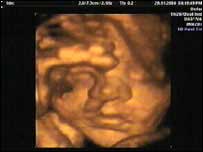

"Initially it was easy, no more miscarriages, no more bereavement, no more having to deal with a child dying," Matt continues. "But after a while it started to dawn on me that I didn't know what to do with the next 20 years of my life." Nikki and Matt have come to terms with the prospect of life without children. "It's a decision we have made that we think is a positive choice," says Nikki. "It's not something that everybody would do, but for us it was really the right thing to do."  | | A scan reassures Clare and Steve that the baby is growing well |

A bouncing baby girlClare and Steve similarly felt overwhelmed by the pressure of trying again for a child. Thankfully they tried again. At 31 weeks pregnant, a scan showed a clear image of their unborn baby's face and even predicts the birth weight. "After everything we've been through, I can't believe we've seen the face of our unborn child," says Steve. | Sources of help and support | The Miscarriage Association c/o Clayton Hospital Northgate Wakefield West Yorkshire WF1 3JS